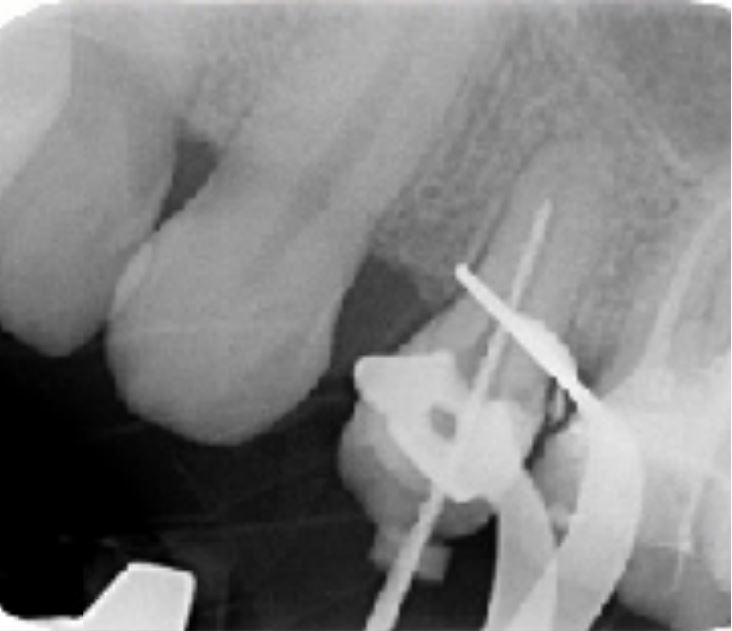

Cas clinique n°2

Dr Hetzel Rémy (Bourgoin Jallieu)

"Traitement initial 16"

Radio pré-opératoire

Première molaire 16 présentant une image radio-claire au regard des racines mésiales et palatines

Test de vitalité négatif

Pansement en place et dent ouverte en urgence en milieu hospitalier

Séquence opératoire

Détermination de la longueur de travail à l'aide de lime manuelle K10

Alésage du système canalaire à l'aide de la séquence FANTA ROTARY jusqu'à la dernière lime 30/04%

Lime apical maitresse de 30/100ème